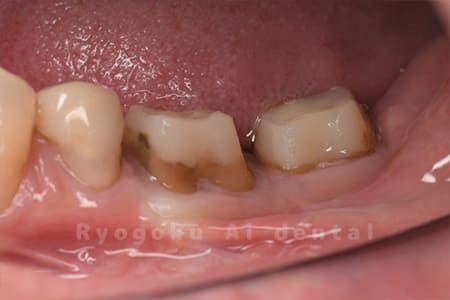

Case03

-

- 原因

- 重度縁下カリエス

- 治療期間

- 約2ヶ月(最終補綴装着まで含む)

- 治療内容

- クラウンレングスニング+歯周外科

- 治療費用

- 44,000円(最終補綴を除く)

他院で抜歯を宣告された患者様です。虫歯が歯茎の中まで及んでいたため、歯周外科・クラウンレングスニングを行い、保存を行いました。